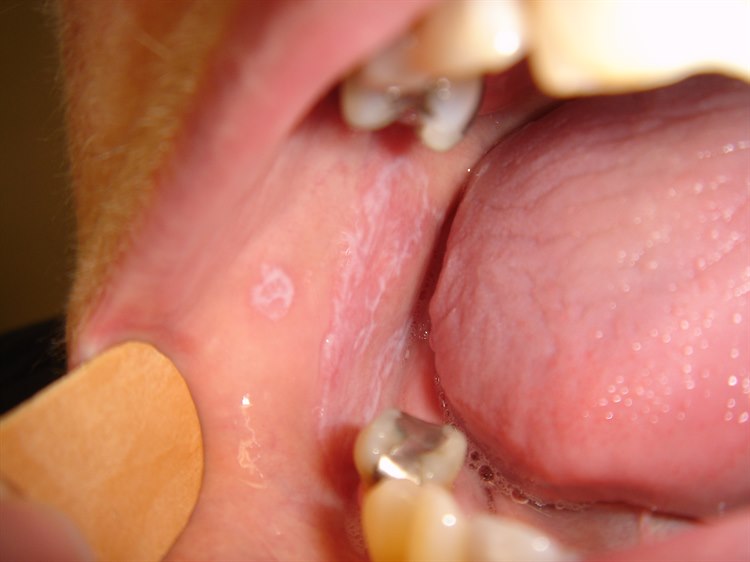

Die Erkrankung äußert sich durch eckige, flache Hautveränderungen, die stark jucken. Häufig sind auch die Schleimhäute betroffen. Dies zeigt sich am häufigsten an der Innenseite der Wangen, wo weiße Flecken und Streifen zu sehen sind (siehe Lichen planus in der Mundhöhle).

Merkmale der Schleimhautveränderungen im Mund

- Der orale Lichen planus zeigt sich meist als weiße Flecken und netzartige Streifen, die die Wangenschleimhaut oder die Zunge befallen können.

- Auch rote Flecken und wunde Stellen können auftreten.

- Schleimhautveränderungen können das einzige Zeichen der Erkrankung sein.

- Die Flecken können keine Beschwerden verursachen oder brennend und schmerzhaft sein.